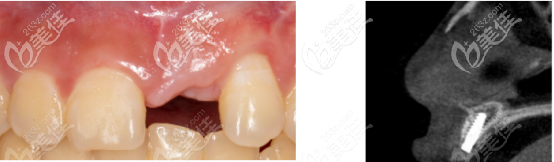

上圖是術前拍攝的ct,從圖中可以看出,嵴頂?shù)街胁抗橇扛静粔颍圆蛔阋灾畏N植體。

為什么這位患者門牙種植需要植入骨粉,原因有以下兩個:

1、當醫(yī)生分離黏膜骨膜瓣后,根據(jù)鄰牙的釉牙骨質界得出,嵴頂骨量不夠植入3.5mm的種植體。

2、用35N的扭力植入Nobel Active? 3.5×11.5植體后,表面有部分暴露,所以用了0.25gbio-oss骨粉(上圖白色為骨粉)進行填充,并且修剪成L型,然后采用無張力縫合法縫合。